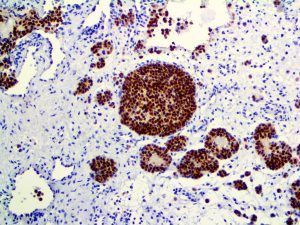

It is the ICU physician who is most likely to witness one of the deadliest manifestations of the abnormal immunological response, the cytokine storm syndrome (CSS). This response is also referred to by some as the cytokine release syndrome (CRS). CSS is characterized by continuous activation and expansion of macrophage and lymphocyte populations, which secrete large amounts of cytokines, causing the cytokine storm. This massive cytokine release is akin to hemophagocytic lymphohistiocytosis (HLH) disease, a syndrome characterized by initial unchecked and persistent activation of cytotoxic T lymphocytes and NK cells.

Clinical and laboratory manifestations of HLH include fever, enlarged liver and/or spleen, neurologic dysfunction, coagulopathy, liver dysfunction, cytopenias (i.e., low levels of erythrocytes, leukocytes, and/or platelets), hypertriglyceridemia, hyperferritinemia, hemophagocytosis, and eventually diminished NK cell activity as the immune system becomes progressively paralyzed. HLH can be familial (primary HLH) or secondary to another disease process (sHLH), such as rheumatic disease, in which it is referred to as macrophage activation syndrome (MAS, characterized by elevated ferritin).